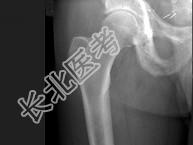

- 单项选择题男,56岁, 右髋部疼痛,5年前被确诊为前列腺癌, 结合图像,最可能的诊断是 ( )

A、骨纤维异常增殖症

B、转移性骨肿瘤

C、畸形性骨炎

D、内生软骨瘤

E、非骨化性纤维瘤